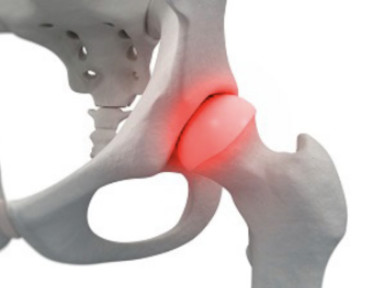

연골의 노화로 인해 연골이 닳으면 골관절염이 발생할 수 있습니다. 골관절염은 관절 외상과 감염성 관절염과 같은 원인으로 발생할 수 있으며 이러한 골관절염은 고관절 통증을 유발할 수도 있습니다.

무혈관성 괴사는 혈액 순환에 문제가 생겨서 뼈가 손상되는 질병으로, 대퇴골두 무혈관성 괴사는 허벅지 뼈인 대퇴골의 머리 부분에 혈액 공급이 원활하지 못해 일어납니다. 이 질병은 주로 30~50대에서 발생하며, 남성에 더 많이 나타납니다. 60% 이상의 환자가 양쪽 고관절의 대퇴골두 무혈관성 괴사를 겪습니다. 이 질병을 일으키는 위험 인자로는 음주, 부신피질 호르몬 투여, 고관절 부위 외상, 잠수병, 통풍, 혈청지질 이상, 만성 신질환, 만성 췌장염 등이 있습니다. 특히 음주와 부신피질 호르몬제가 전체 원인의 90% 정도를 차지합니다.